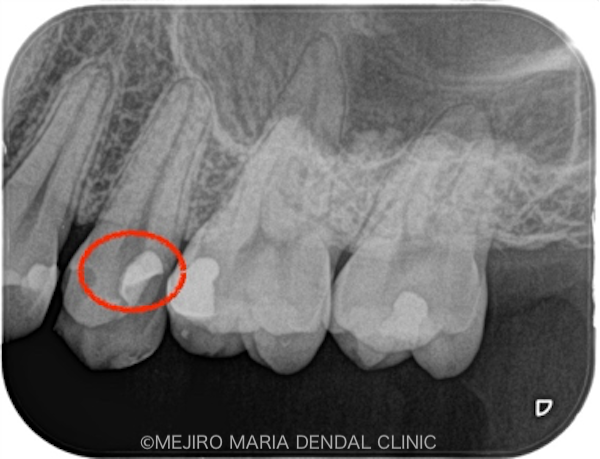

前医で充填された歯科用素材を除去後(写真1)、さらに虫歯が確認できて、容易に露髄(神経に到達すること)しました。

洗浄液と適切な止血によって、歯髄からの出血をコントロールできた(写真2)ことから、炎症組織は取りきれたと判断し、当日に予定どおり「生活歯髄保存療法」を行い、経過を確認していくこととしました。